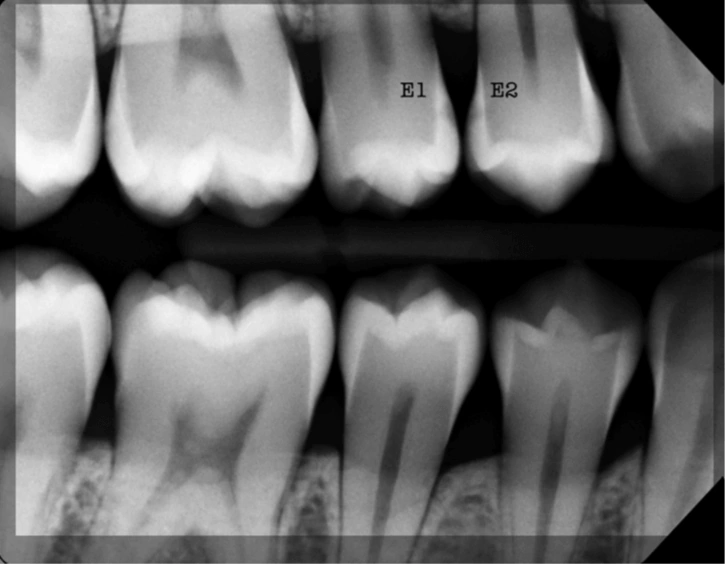

Según la institución, uno de los mayores desafíos es distinguir la dentina infectada que debe retirarse de la que, aunque dañada, aún puede conservarse. Los métodos actuales, como los tintes especiales, alargan el proceso y requieren pasos adicionales.

El nuevo aparato utiliza una sonda óptica que se aplica sobre la superficie del diente. Registra la fluorescencia del tejido y envía los datos a un ordenador, donde un modelo de aprendizaje automático identifica de inmediato el tipo de dentina.

Este método permite un diagnóstico más rápido y preciso, sin necesidad de procedimientos invasivos ni prolongaciones innecesarias en la atención.